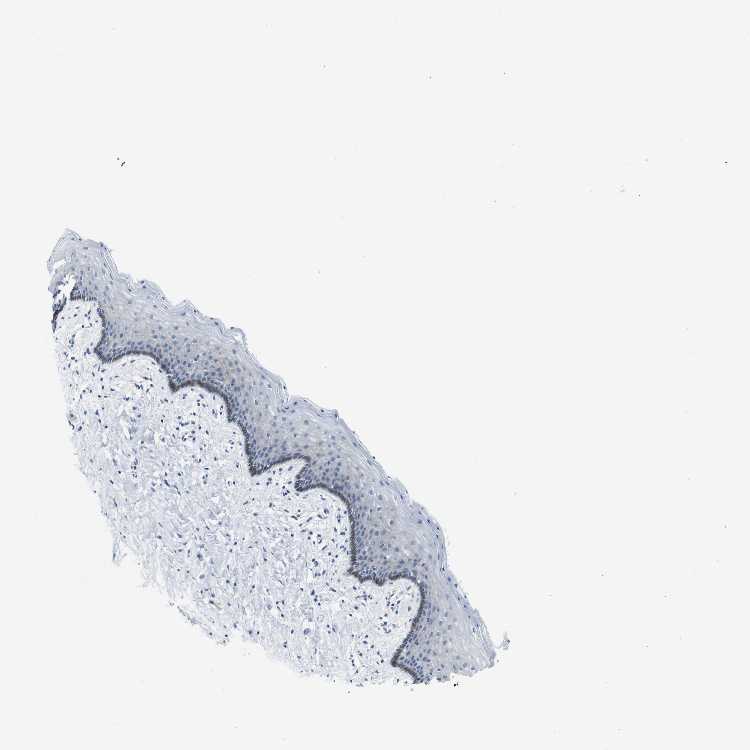

TISSUE PRIMARY DATA VAGINA Show tissue menu

VAGINA - Antibody stainingi

Antibody staining in the annotated cell types in the current human tissue is reported as not detected, low, medium, or high, based on conventional immunohistochemistry profiling in selected tissues. This score is based on the combination of the staining intensity and fraction of stained cells.

Each image is clickable and will lead to virtual microscopy that enables deeper exploration of all samples and also displays staining intensity scores, fraction scores and subcellular localization as well as patient and tissue information for each sample.

Antibody CAB013249Antibody CAB015179

Squamous epithelial cells LowMedium